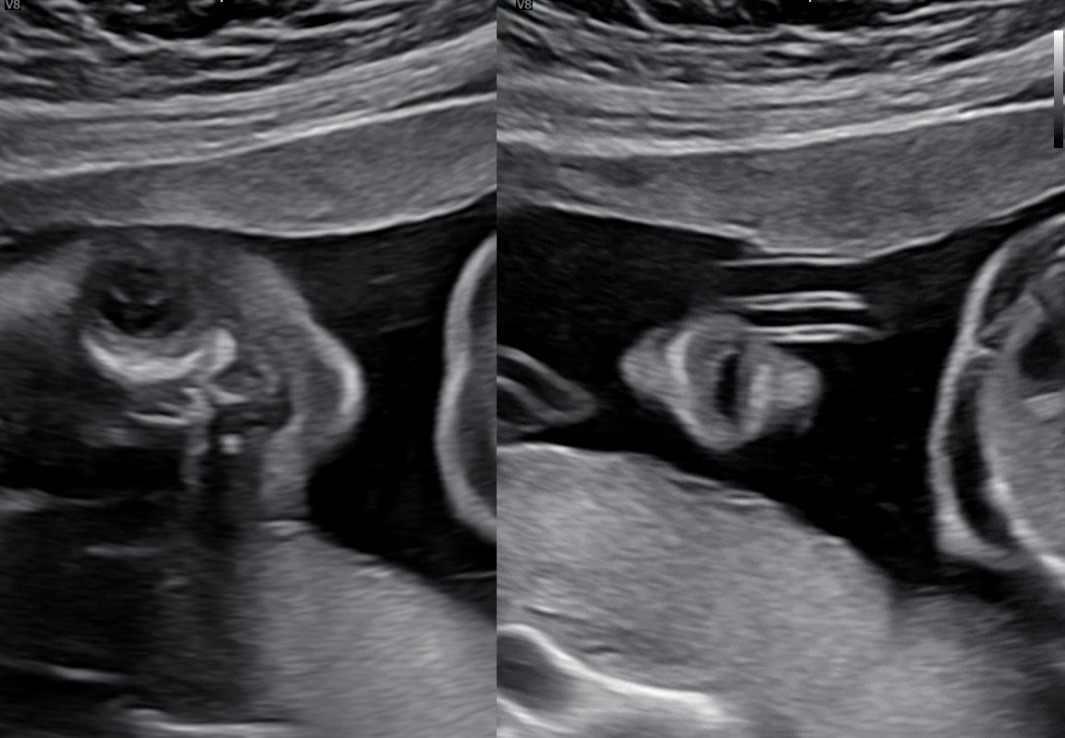

21주차 우리 애기. 왼쪽이 눈 오른쪽이 코랑 입이다. 벌린 입이 너무너무 귀여워서 이 영상을 캡쳐해 여러 번 돌려봤다. 남편은 봐도 잘 모르겠다고 한다(왠지 서운 ㅠ) 그래도 엄마 눈엔 다 보여 빵빵아‪‪‬‪‪‬

21주차 우리 애기. 손으로 얼굴을 감싼 게 내눈에는 딱 보여서 너무 귀엽다고 남편 보내줬는데 남편은 또 잘 모르겠다고 한다 ㅠㅠ 답답한 마음에 붉은선으로 눈코입 손 표시해준 사진 ㅋㅋㅋㅋㅋㅋ 남편은 그래도 모르겠다고!!!! ㅋㅋㅋ 왜 저게 안 보여~~ 우리 애기 너무너무 순하게 자고 있는데! ㅋㅋㅋ